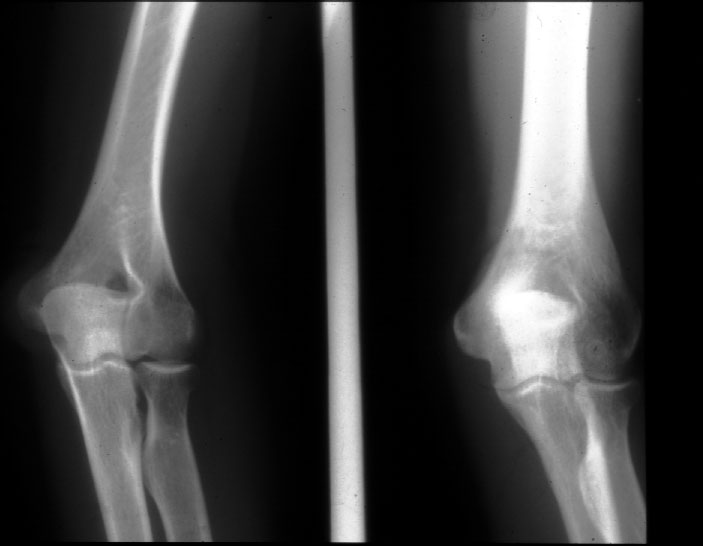

Normal Elbow (AP and oblique) -- Identify: humerus, radius, ulna, medial

and leteral epicondyle, capitulum, radial head, radial tuberosity